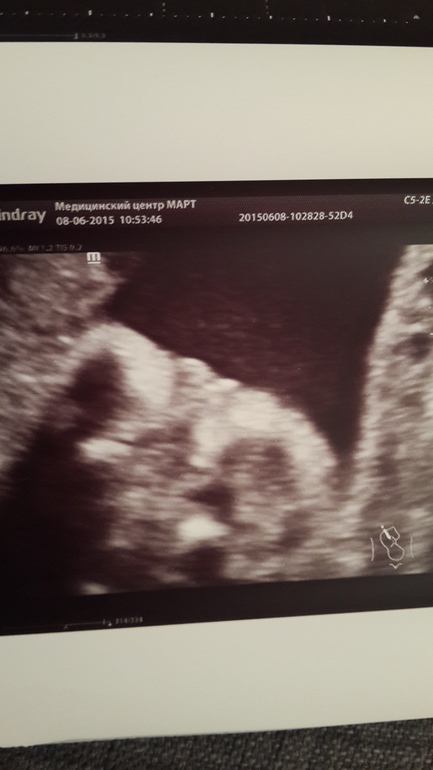

Сходили на узи! Развеяли страхи. Фото прилагается.

а мы их как отрастили!))) Ставили опоздание бедренных костей на втором скрининге, сегодня сходила на узи (до третьего скрина ещё месяц) и вуаля! - наши ноги опережают теперь на неделю срок беременности))) отрастили))) а ведь это там как маркёр лепили...

и теперь уже точно подтвердили девочку. Мой кружок стал розовым! Папа рад, аж сам не свой! А ещё он сегодня первый раз почувствовал пинок (не мог до этого понять, плацента по передней стенке) так после этого его совсем накрыло. Еле его в чувства привели))))

Девица наша уже перевернулась головой в низ и совершенно не стесняясь во всей красе нам пирожок выставила)))